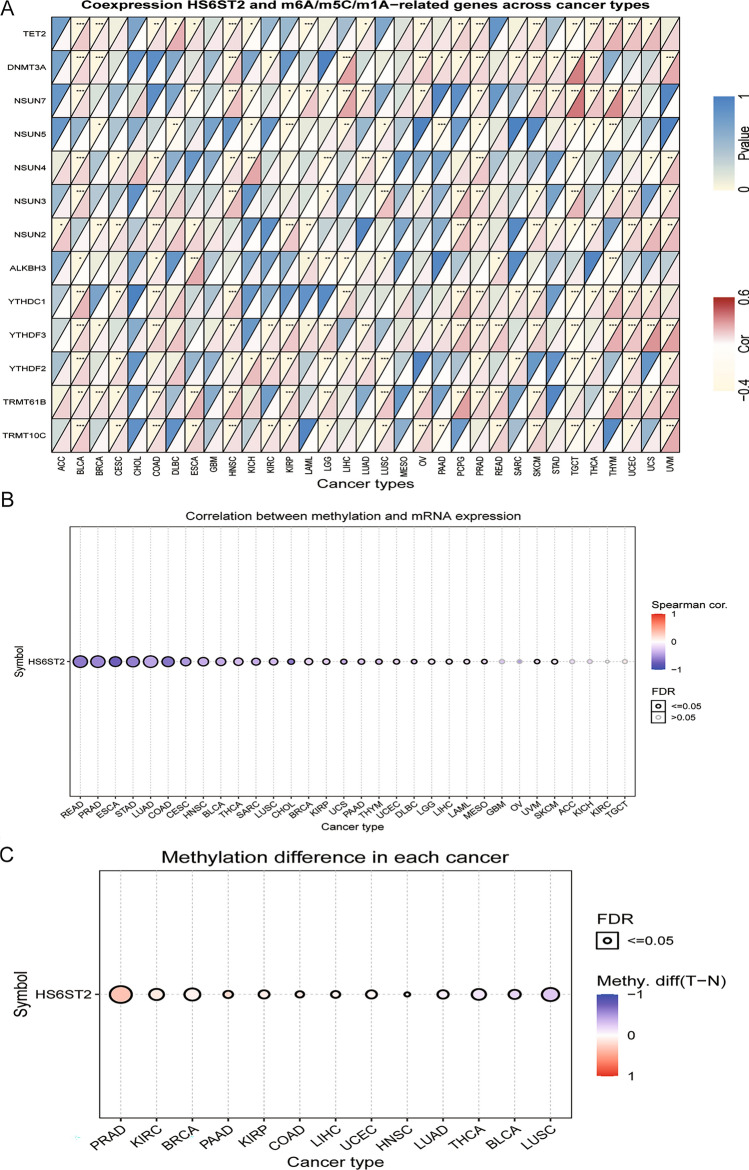

HS6ST2 is associated with DNA methylation and the expression of RNA methylation-associated genes across cancers

RNA methylation modification, including m1A, m5C, and m6A, occurs in a variety of RNAs, with varying effects on RNA function29. Positive associations were discovered between HS6ST2 and TET2 and DNMT3A in BLCA, prostate adenocarcinoma (PRAD), BRCA, head and neck squamous cell carcinoma (HNSC), THCA, and skin cutaneous melanoma (SKCM) when we calculated their expression levels with respect to other RNA methylation-related genes (Supplementary Table S1). HS6ST2 expression was negatively correlated with NSUN4 and YTHDF2 in LUSC, testicular germ cell tumors (TGCT), and brain lower grade glioma (LGG) but positively correlated with NSUN4 and YTHDF2 in BLCA, cervical squamous cell carcinoma and endocervical adenocarcinoma (CESC), HNSC, KICH, uveal melanoma (UVM), LUAD, and PRAD (Fig. 2A). Similarly, the expression of YTHDC1 and YTHDF3 was negatively correlated with HS6ST2 in TGCT, but positively correlated with HS6ST2 in BLCA, COAD, UCEC, HNSC, PCPG, PRAD, SKCM, uterine carcinosarcoma (UCS), and thymoma (THYM).

Changes in DNA methylation have been identified in a variety of malignancies and are considered a cause of carcinogenesis30. By evaluating the relationship between promoter methylation and HS6ST2 expression in GSCA data, significant relationships between gene expression and methylation were found in 26 distinct cancer types (Fig. 2B). Figure 2C shows that HS6ST2 expression was positively correlated with promoter methylation in BLCA, THCA, and LUAD, LUSC but negatively correlated with promoter methylation in BRCA, UCEC, HNSC, COAD, liver hepatocellular carcinoma (LIHC), PAAD, KIRC, KIRP, and PRAD (Supplementary Table S1). The findings indicate that an epigenetically altered state of HS6ST2 may facilitate carcinogenesis.